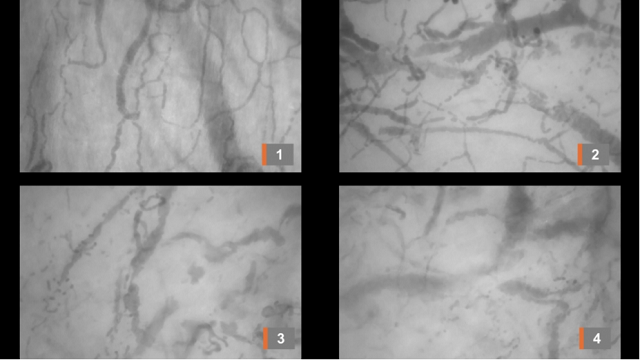

Estudo feito com 13 doentes submetidos à ventilação mecânica reforça a teoria de que distúrbios de coagulação sanguínea resultantes de uma resposta inflamatória exacerbada ao SARS-CoV-2 estariam na base dos sintomas mais severos da doença (a imagem 1 mostra a microcirculação normal; as imagens 2 e 3 registram sinais de problemas na circulação e, a imagem 4, capta a obstrução tromboembólica aguda - Foto: Carlos Henrique Miranda/USP)

O achado, divulgado na plataforma medRxiv, reforça a teoria de que distúrbios de coagulação sanguínea resultantes de uma resposta inflamatória exacerbada ao SARS-CoV-2 estariam na base dos sintomas mais severos da doença – entre eles insuficiência respiratória e fibrose pulmonar. Essa hipótese começou a ganhar força em abril, quando pesquisadores da Faculdade de Medicina da USP em São Paulo encontraram, durante a autópsia de pessoas que morreram em decorrência da COVID-19, microtrombos nos vasos mais finos que irrigam o pulmão (leia mais em: agencia.fapesp.br/32882). “Ainda havia uma certa dúvida se esses distúrbios de coagulação seriam uma consequência do longo período de internação em UTI [unidade de terapia intensiva] ou se de fato eram causados pela resposta inflamatória induzida pelo vírus. Mas nós conseguimos observar a formação dos microtrombos já no primeiro dia de internação”, conta à Agência FAPESP Carlos Henrique Miranda, professor do Departamento de Clínica Médica da Faculdade de Medicina de Ribeirão Preto (FMRP-USP). O artigo, ainda em versão preprint (não revisado por pares), descreve a análise feita na microcirculação sublingual de 13 pacientes que precisaram ser intubados e submetidos à ventilação mecânica. As imagens foram obtidas por meio de um microscópio equipado com uma câmera e uma luz polarizada capaz de destacar as hemácias e os vasos sanguíneos. O estudo foi apoiado pela FAPESP. “Nossa proposta original era usar o microscópio para estudar problemas de coagulação sanguínea em pacientes com sepse [inflamação sistêmica geralmente desencadeada por uma infecção bacteriana localizada]. Mas a pesquisa foi paralisada por causa da pandemia e tivemos dificuldade até para importar o equipamento. Conseguimos graças à ajuda da Gerência de Importação da FAPESP e decidimos voltar nossa atenção aos pacientes com COVID-19”, diz Miranda.

Foto - Pixabay

A região sublingual foi escolhida por ser uma área de mucosa possível de ser acessada de forma não invasiva. “Observamos nesses pequenos vasos múltiplas falhas de enchimento, ou seja, trechos sem nenhuma hemácia. Inferimos que nessas regiões existem trombos obstruindo o fluxo sanguíneo. Em alguns dos pacientes conseguimos ver o vaso trombosando bem na nossa frente”, relata o pesquisador. De acordo com Miranda, o distúrbio de coagulação causado pelo SARS-CoV-2 parece ter um “caráter predominantemente trombótico e muito intenso”, diferente do que se observa na sepse bacteriana. No caso da COVID-19, o problema está associado ao que se chama de tempestade de interleucinas (proteínas que atuam como sinalizadores imunes), que ativa um processo conhecido como cascata de coagulação. As plaquetas presentes na circulação começam a se agregar, os trombos formados obstruem os pequenos vasos do pulmão e causam microinfartos. As regiões do tecido que morrem por falta de irrigação dão lugar a tecido cicatricial – processo conhecido como fibrose. Além disso, os microtrombos que se formam na interface do alvéolo pulmonar com os vasos sanguíneos impedem a passagem do oxigênio para as pequenas artérias, prejudicando a oxigenação do sangue (leia mais em: agencia.fapesp.br/33175). “Esses fatores inflamatórios que levam à formação dos microtrombos são sistêmicos e, portanto, não afetam apenas o pulmão. Pode haver prejuízos em diversos órgãos. Nós conseguimos registrar os efeitos na região da língua”, explica Miranda. Atualmente, o pesquisador coordena um estudo clínico com heparina, um dos medicamentos anticoagulantes mais usados no mundo. O objetivo é ver se o tratamento ajuda a melhorar a oxigenação do sangue de pacientes com insuficiência respiratória causada pelo novo coronavírus. “Pretendíamos registrar com o microscópio o efeito do tratamento na microcirculação sublingual, mas a epidemia estourou aqui na região de Ribeirão Preto e a prioridade agora é atender os doentes”, diz o pesquisador. O artigo In vivo demonstration of microvascular thrombosis in severe Covid-19 pode ser lido em: www.medrxiv.org/content/10.1101/2020.07.09.20149971v1.